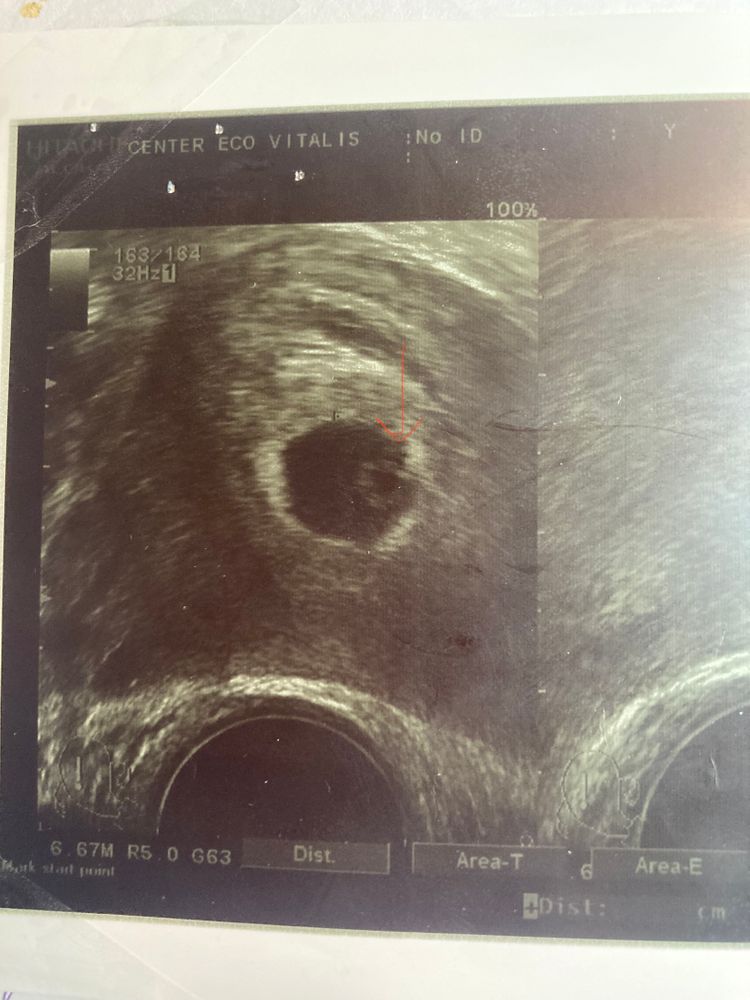

Эмбрион четко не визуализируется

В заключении написали «эмбрион четко не визуализируется», но во время узи врач увидела «бриллиантик» на «кольце» (жм)… как думаете, похоже на эмбриончика?

Анастасия, по узи 5-6 недель, по первому дню последних месячных - ровно 6 акушерских получается.